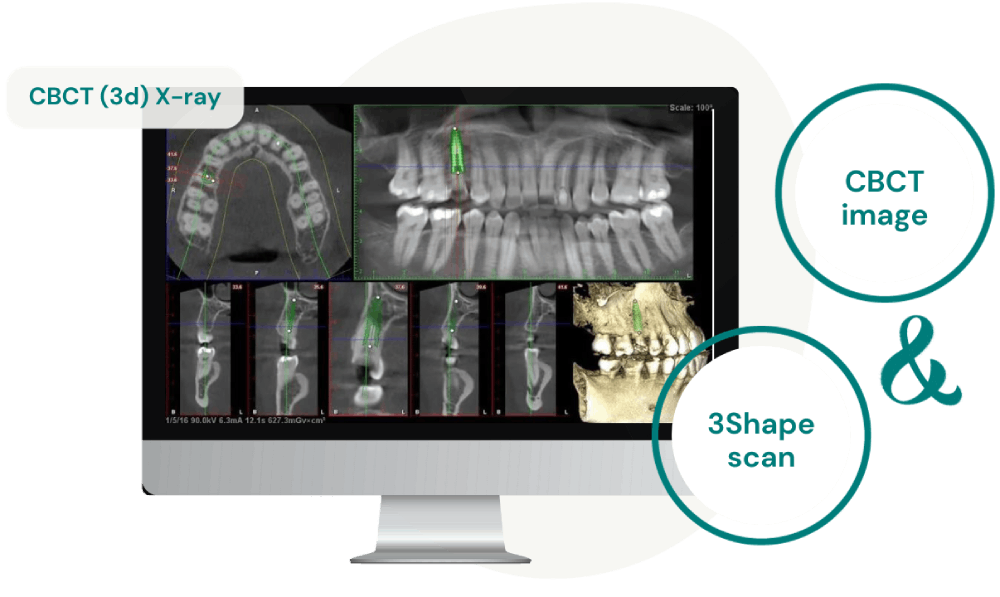

Immagine CBCT e Scansione 3Shape

Utilizziamo una combinazione di immagini CBCT e scansioni 3Shape per creare un modello chirurgico personalizzato, che ci permette di posizionare gli impianti con precisione.

La CBCT è una tecnologia di imaging specializzata che fornisce immagini tridimensionali dettagliate delle strutture della mascella, consentendoci di ottenere immagini molto precise delle strutture orali e maxillo-facciali. Queste immagini sono fondamentali per elaborare un piano di terapia implantare personalizzato. Con questo piano, realizziamo un modello chirurgico, che è la base per l’inserimento degli impianti.